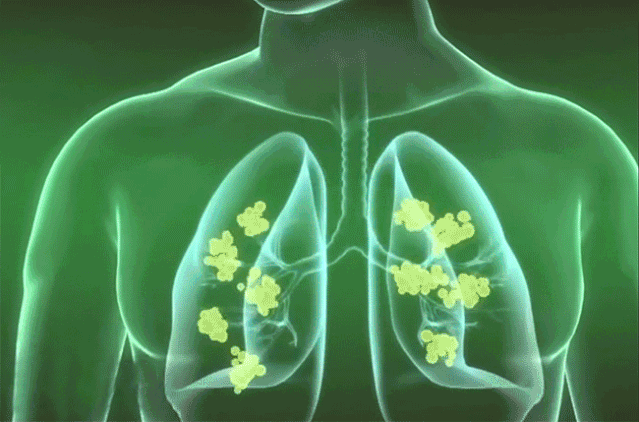

(橘紅顆粒)神奇的地方就是因為它有(化死痰)的效果!將氣管和肺泡內的死痰,都化成水,排除體外,咳喘病自然好了,而且不再复發

死痰是咳喘疾病反復發作的根源。

當死痰黏在氣管、支氣管時,患者出現氣管刺癢、咳嗽、痰咳不出、吐不淨、

喘氣像拉風箱一樣的呼哧呼哧的響,以及睡覺不能平躺等症狀。

當死痰蔓延到肺部深處,粘在肺泡上時,肺泡就會破裂,氣體交換受阻,

人體開始缺氧,出現氣憋胸悶、面唇紫暗等,若死痰還不能及時清除,

就會進而造成肺部動脈高壓,導致肺心病,患症狀者可能隨時猝死!